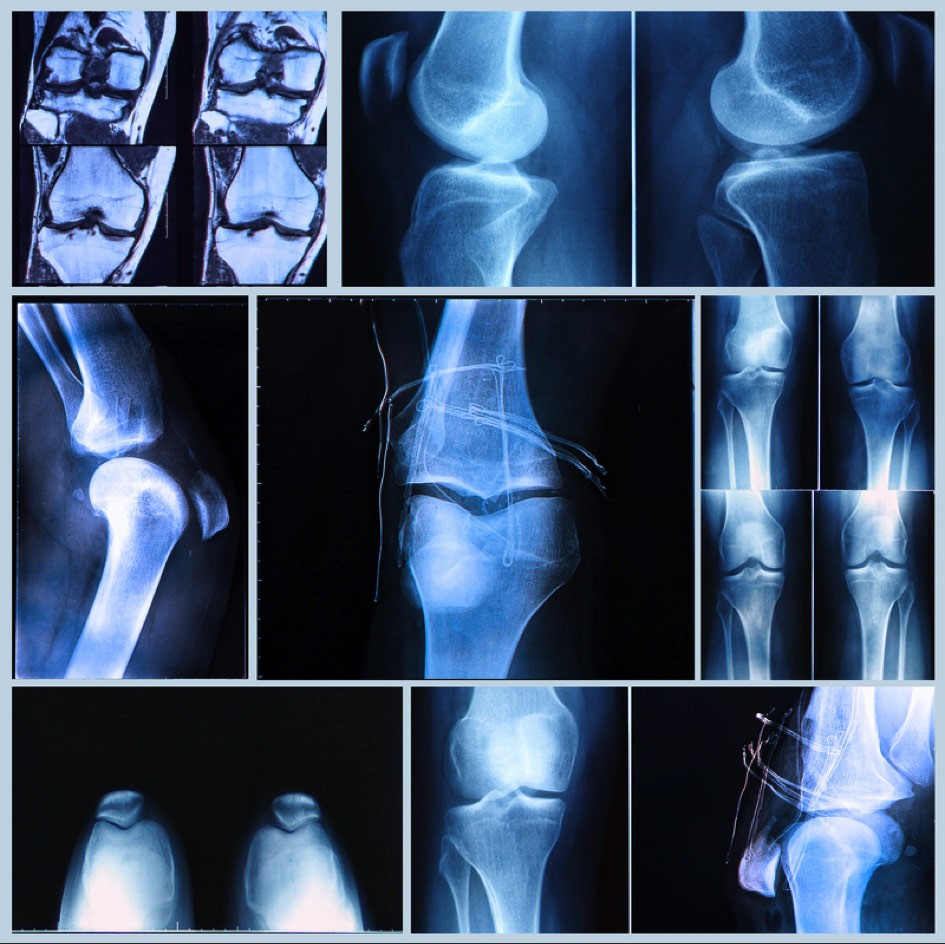

ANOVA Stammzelltherapie für Knie-Verletzungen und -Degeneration

Sowohl Knieverletzungen als auch degenerative Veränderungen im Knie sind oft schmerzhaft und langwierig. Da das Knie ein sehr komplexes und vielfach beanspruchtes Gelenk ist, kommen Verletzungen häufig vor, aber es gibt bisher oft nur sehr begrenzt wirksame Therapieoptionen. Knie-Arthrose oder Knie-Arthritis werden meist zuerst medikamentös und dann mittels eines Gelenkersatzes behandelt. Wenn z.B. Knieschmerzen und ein unangenehmes Spannungsgefühl in der Kniekehle Ihre Symptome sind, kann es sich um die sogenannte Bakerzyste (oder Baker-Zyste) handeln. Eine weitere, häufige Knieverletzung ist der Meniskusriss oder Risse im vorderen oder hinteren Kreuzband. Solche und weitere Fälle erfordern eine effektive und schnelle Behandlung. Regenerative und zelluläre Therapien gegen Schmerzen im Knie sind dringend erforderlich, sowohl zur Behandlung von Knieverletzungen als auch für altersbedingte degenerative Knieprobleme. Die Behandlung von Knieproblemen gehört zu den am häufigsten angewandten und erforschten Bereichen für stammzellbasierte Therapien. ANOVA bietet ein einzigartiges Therapieprogramm aus Knochenmarkkonzentrat und PRP-Injektionen. Unsere Therapieprogramme basieren auf Ihrem individuellen Zustand und sind auf eine optimale regenerative Wirkung für Sie ausgelegt.

Wir begutachten gerne Ihre bisherigen medizinischen Unterlagen und Befunde sowie Bilder (MRT, Röntgen, CT). Dies erfolgt immer, wenn Sie an einer Behandlung interessiert sind, aber wir beraten Sie auch, wenn Sie eine Zweitmeinung zu Ihrer konservativen Behandlung wünschen. Nutzen Sie unsere diagnostische Kompetenz! Unsere Patientenbetreuer informieren Sie darüber, welche Informationen wir vorab benötigen, wie Sie uns Ihre Unterlagen zukommen lassen können, und terminieren dann einen Beratungstermin mit unseren Ärzten. Bitte nutzen sie unser Kontaktformular um eine schnelle Bearbeitung zu erleichtern. Der Beratungstermin kann über eine Videokonferenz oder telefonisch erfolgen. Wenn Sie eine intensivere Beratung oder zusätzliche diagnostische Untersuchungen wünschen, können Sie auch einen persönlichen Beratungstermin vor Ort in Offenbach vereinbaren. Alle Gespräche mit unseren Patientenbetreuern und wissenschaftlichen Experten sind kostenfrei. Sie werden bei Arztgesprächen vorab über entstehende Kosten informiert.